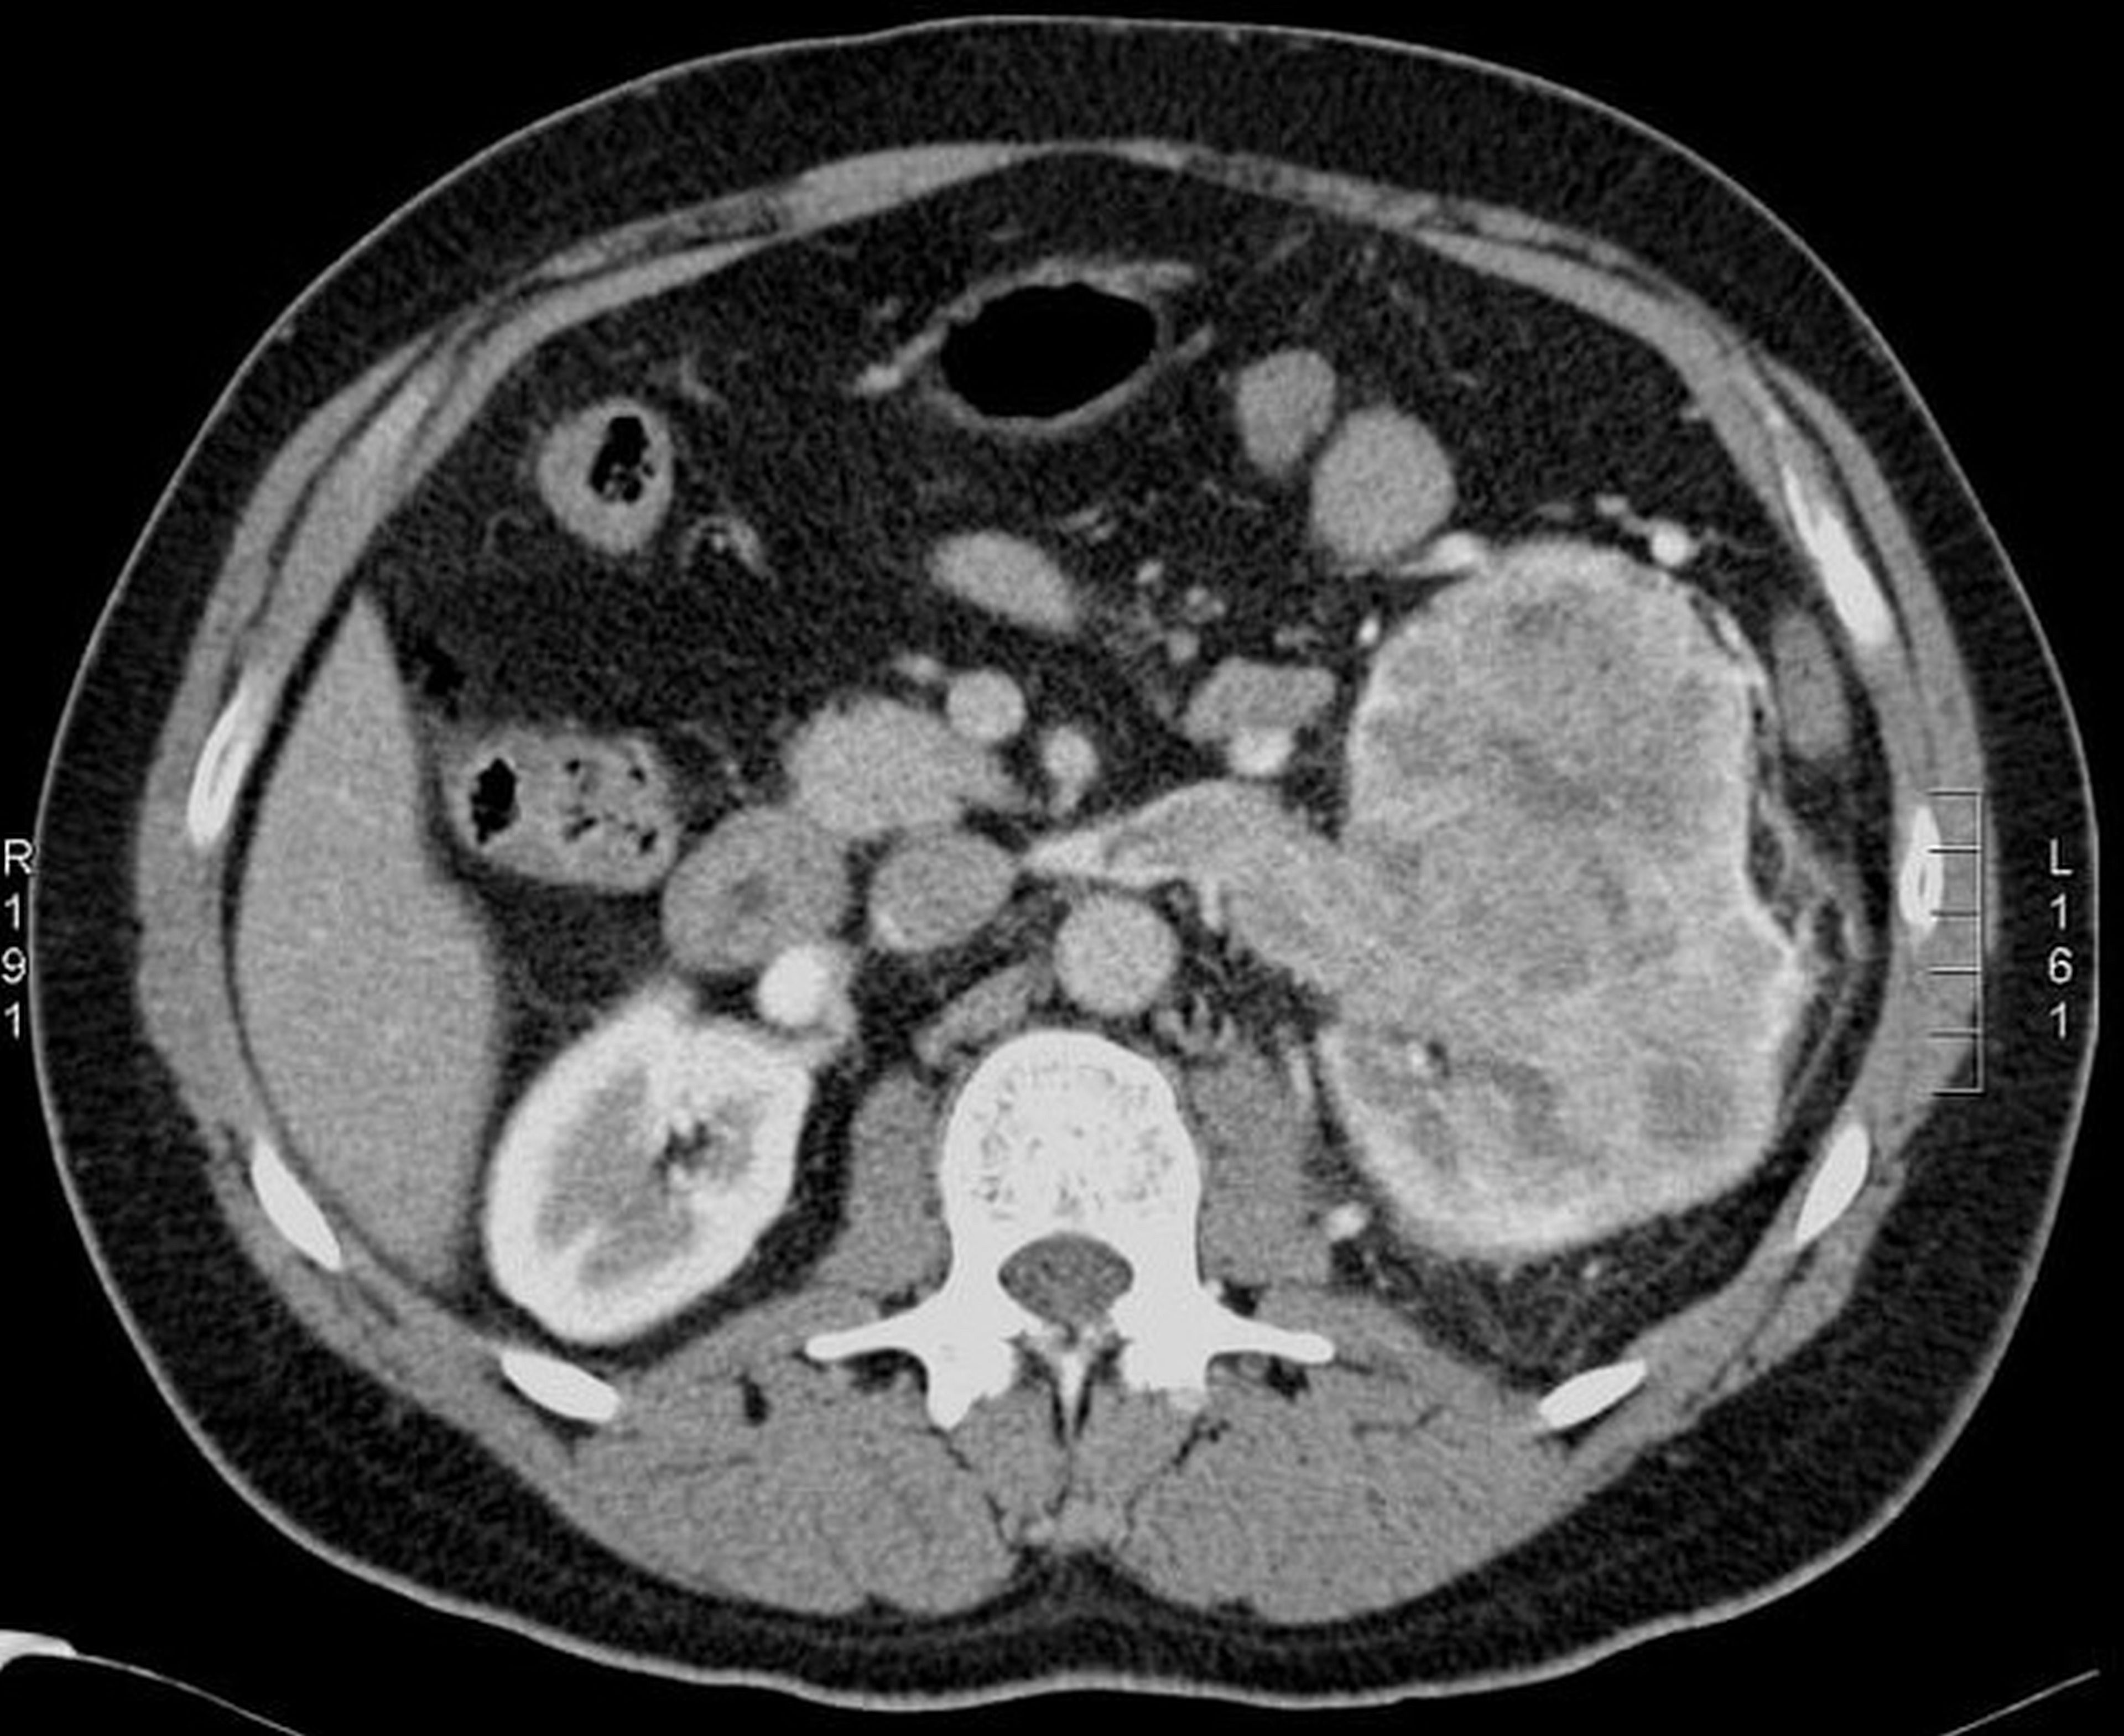

There are several types of cancer that can affect the kidneys. Renal cell carcinoma (RCC), is the most common form and accounts for approximately 85% of all kidney cancers. In RCC, malignant cells develop in the lining of the kidney's tubules and typically grow into a mass called a tumour. The earlier kidney tumours are discovered, the better a patient's chances for survival. Tumours discovered at an early stage often respond well to treatment. Survival rates in such cases are high. Tumours that have grown large or spread to other parts of the body are much more difficult to treat and present a greatly increased risk to patients life.

Patients who have loin pain, blood in urine or a vagulely felt lump in upper abdomen are likely to have kidney cancer. It is important to consult a nearby doctor to get ultrasound scan followed by a specialist consultation to decide on further course of action.